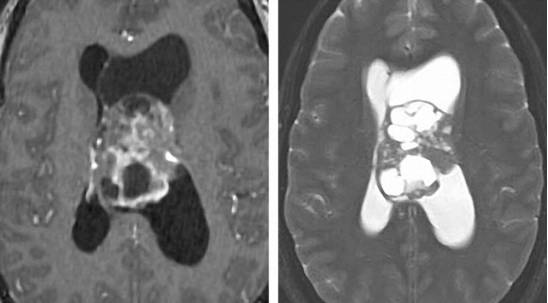

图2. 颅咽管瘤在MR图像上表现为不均匀的囊性和实质性信号(上图)。其囊性成分在T1相上表现为高信号,结节部分则表现为不均匀的显著强化(左下图)。CT上表现为点状钙化(右下图)。